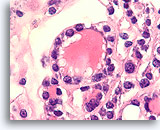

Afbeelding 13

Benigne, hyperplastisch/adenomatoïde nodule, schildklier FNA, celblok.

Het celblok dat overeenkomt met afbeelding 11-12 toont een duidelijk bijvoeging van micro- en macrofollikels. Er zijn twee kenmerken die voor een benigne nodule pleiten. Het eerste is dat de microfollikels afgeplat cytoplasma vertonen, vergeleken met de robuuster uitziende macrofolliculaire cellen (vergelijk de hoogte van het cytoplasma bij de twee pijlen). Een tweede kenmerk is de variatie in het uiterlijk van het colloïd tussen de verschillende follikels. Let op het oedemateuze colloïd in het ene follikel dat zich naast een follikel bevindt met dicht opeengepakt colloïd (open pijlen). Van benigne hyperplastisch/adenomatoïde nodulen wordt verwacht dat ze heterogeniteit vertonen, terwijl folliculaire neoplasmen monotoner zijn.

40X

Afbeelding 13

Benigne, hyperplastisch/adenomatoïde nodule, schildklier FNA, celblok.

Het celblok dat overeenkomt met afbeelding 11-12 toont een duidelijk bijvoeging van micro- en macrofollikels. Er zijn twee kenmerken die voor een benigne nodule pleiten. Het eerste is dat de microfollikels afgeplat cytoplasma vertonen, vergeleken met de robuuster uitziende macrofolliculaire cellen (vergelijk de hoogte van het cytoplasma bij de twee pijlen). Een tweede kenmerk is de variatie in het uiterlijk van het colloïd tussen de verschillende follikels. Let op het oedemateuze colloïd in het ene follikel dat zich naast een follikel bevindt met dicht opeengepakt colloïd (open pijlen). Van benigne hyperplastisch/adenomatoïde nodulen wordt verwacht dat ze heterogeniteit vertonen, terwijl folliculaire neoplasmen monotoner zijn.

40X